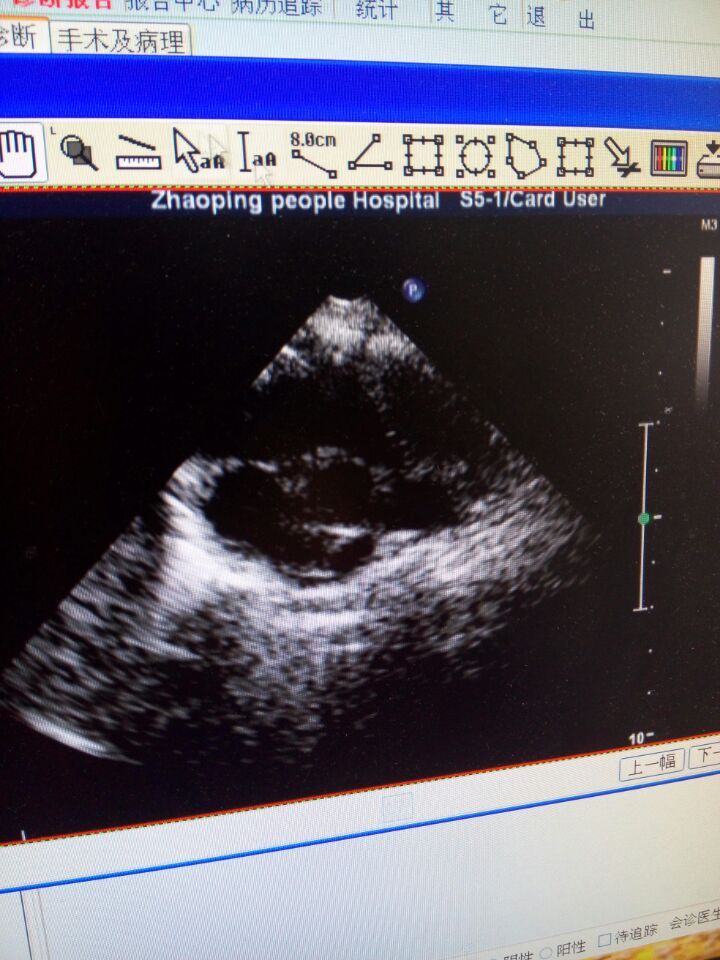

平时哭出现紫绀,没力气吃奶,易出现喉响、出汗,活动是明显,去医院做了B超肺动脉狭窄厉害才约0.3cm,主动脉骑跨约50%,室缺1.7cm,右室大,悲伤至极,想问问专家现在能手术吗?想去上海儿童医学中心手术?但农村的没出过门,希望得到好心人帮助